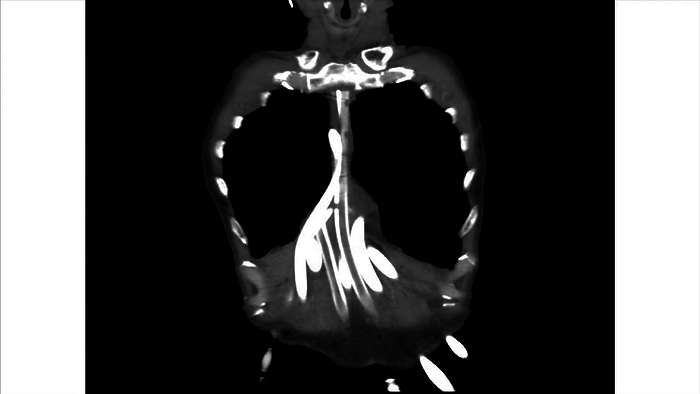

13.

这是他的电脑断层扫描,理论上,胸腔里应该有一颗心脏,可是现在没有心脏,只看到一些管子。

十六天以后,我们给这个病人做心脏移植。

这是心脏外科教授王水深给我看的。他说,锯胸以后,没有看到心脏,只看到一些塑胶管子,接到外面的叶克膜上。